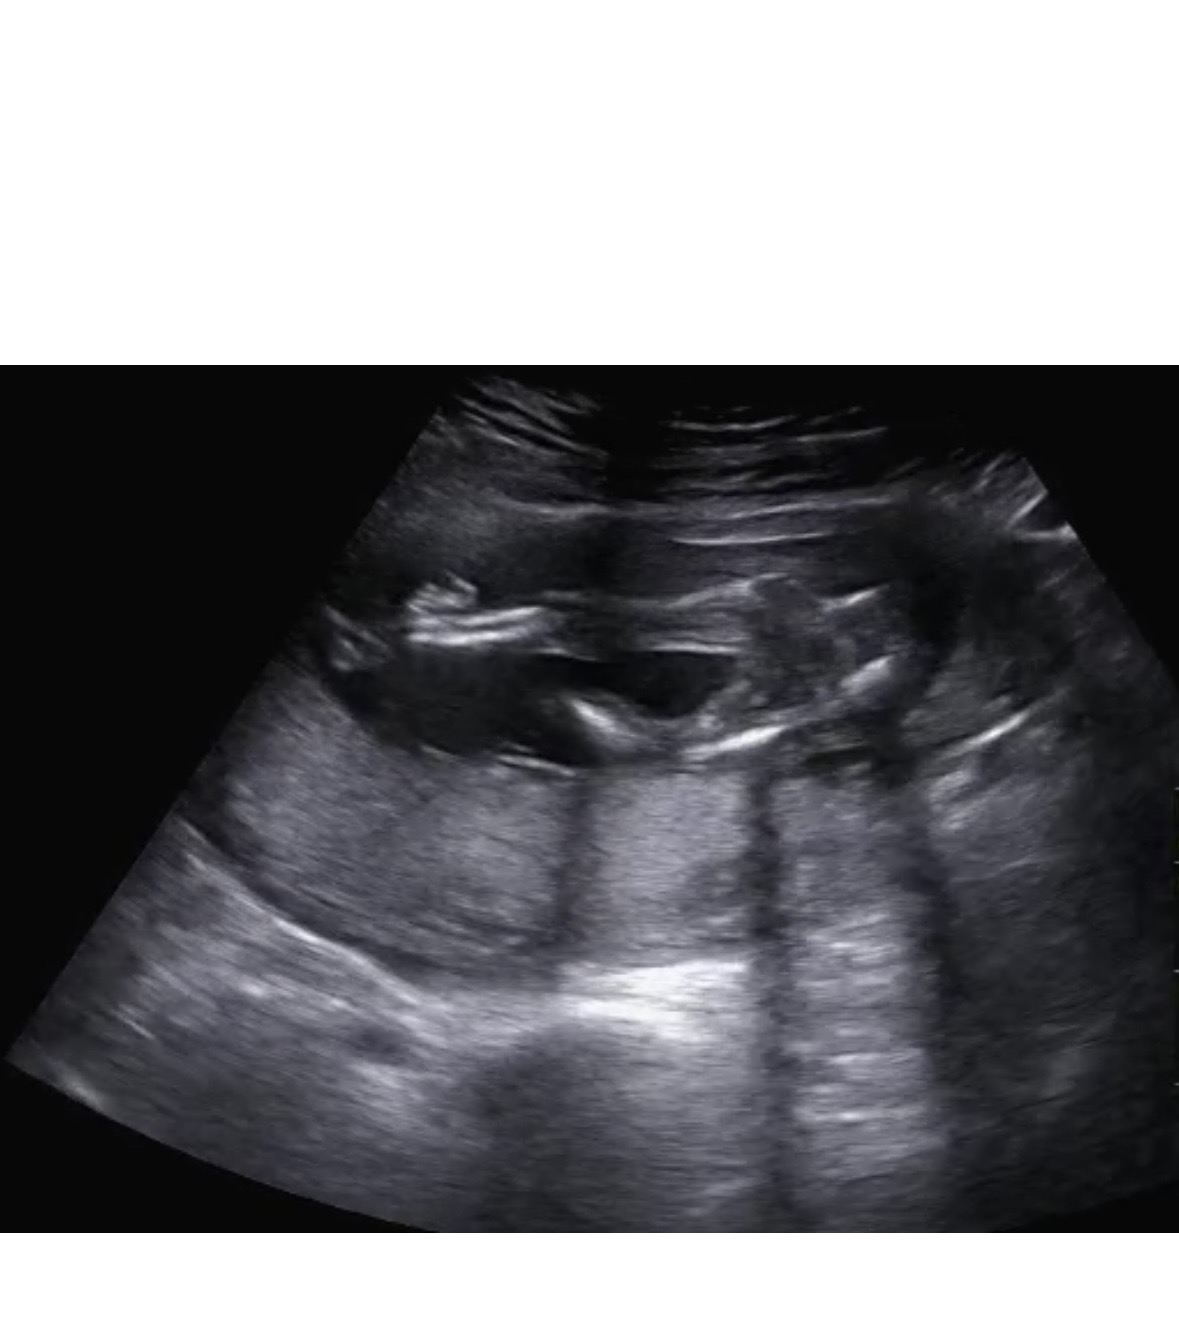

16주인데 성별 너무 헷갈려서요ㅠㅠ 도와주세요ㅠㅠ

16주 촘파 보고왔는데 고수님들 도왖 세여ㅠㅠ